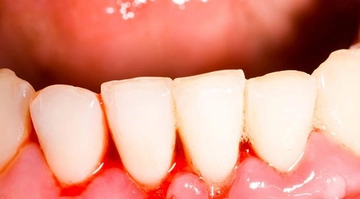

Diş ekimi, günümüzde oldukça yaygın bir işlem olmasına rağmen, her cerrahi müdahalede olduğu gibi bazı riskleri de beraberinde getirebilir. Enfeksiyon ve vücut reddi, bu işlemin potansiyel komplikasyonları arasında yer alır. Ancak, bu riskler uygun önlemlerle önemli ölçüde azaltılabilir.

- Ağız Hijyeni: İşlem sonrası ağız hijyenine özen göstermek enfeksiyon riskini azaltır. Ancak, işlem bölgesine doğrudan zarar vermemek için nazik davranmak gerekir.